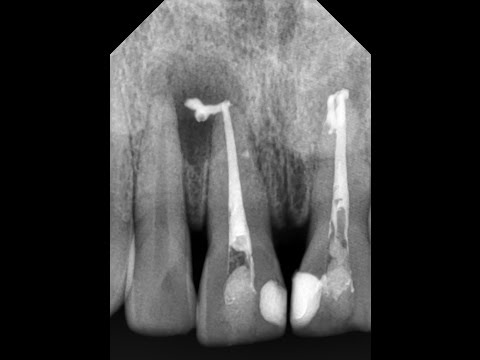

Обратитесь к стоматологу для рентгеновского снимка, чтобы определить точное расположение излишков пломбировочного материала.

Осложнения при лечении корня зуба

Как извлечь сломанный инструмент из корневого канала?

Осложнения при лечении пульпита. Попадание пломбировочного материала за пределы корня зуба

Какой силер лучше? Выход силера за верхушку. Силер в стоматологии